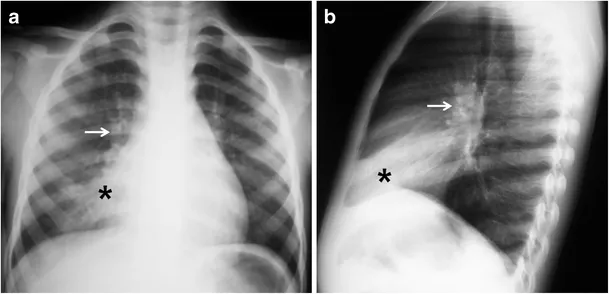

- X-ray: Steeple sign (AP neck).

- X-ray: May show object, unilateral hyperinflation/atelectasis.

- Diagnosis: Clinical; CXR shows infiltrates/consolidation.